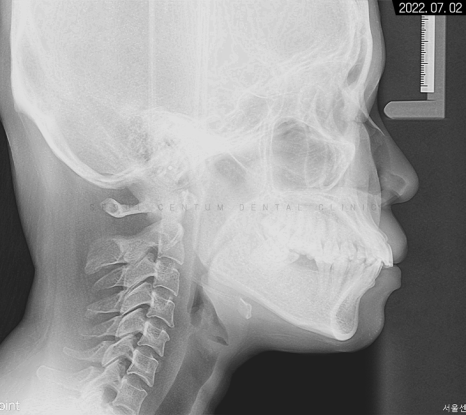

세팔로 사진으로는

잇몸과 치아 전돌 양상이 보이고

에스테틱 라인을 과하게 넘어가 있다는 것을

알 수 있었습니다.

계측점을 분석해 본 결과 정상 범주로 넣기 위해서는

치아 후방 이동이 상당히 필요한 경우였습니다.

뻐드러진 앞니 모양이 보이는데,

이 같은 상태면 앞니 사용이 좋지 않아

식사가 불편하고 아랫니가 잇몸을 자극해서

치주염까지 생길 수 있어 주의해야 합니다.

세팔로 사진으로 보면 전돌 해소가

더 확실하게 된 것을 볼 수 있어요.

에스테틱 라인도 좋아지고

전체적으로 부드러워진 비율이 나타나고 있습니다.

입술이 예전보다 슬립한 형태가 되기도 하셨고요.